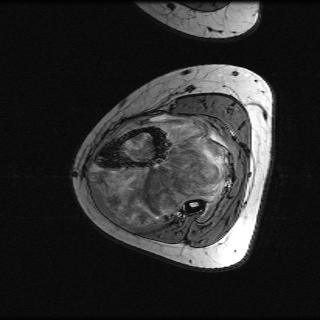

Test data: For evaluation, we used the ten 352352 MRI images in Fig. 2, which were not in the training dataset. The measurements were constructed using (1) with complex AWGN whose variance was adjusted to give a pre-masking SNR of 40 dB. For the multicoil experiments, we used coil sensitivities simulated using the Biot-Savart law, while in the single-coil case, we used .